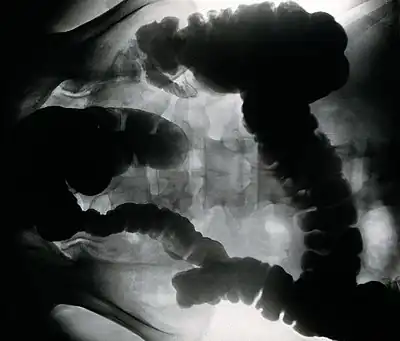

![]() | |